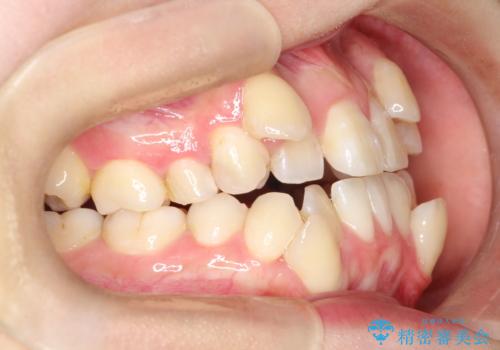

【ワイヤー矯正】八重歯 歯のでこぼこを治したい!

- 治療計画

- 「歯のでこぼこを治したい」を主訴に来院された患者様です。 上下ともに、歯のでこぼこが強く、上下左右4の抜歯をし、ワイヤー矯正で治療を行いました。

かなり綺麗に並ぶ事ができ大変満足していただけました。

叢生量がかなり多かったのですが、歯肉退縮も失活歯も無くとても綺麗な歯並びになりました。